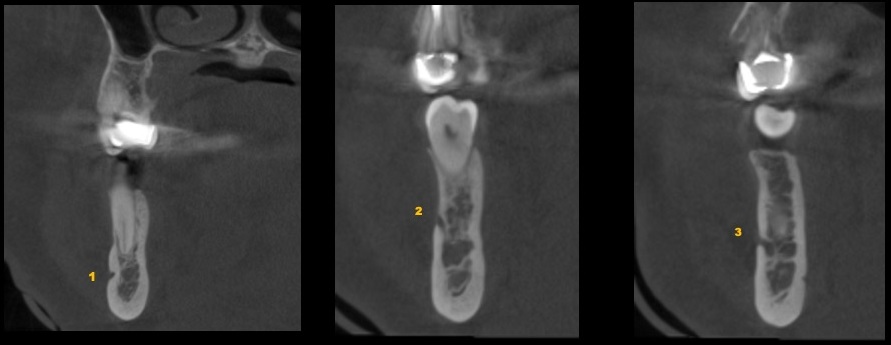

Paciente femenino de 53 años acude para una evaluación general. A la evaluación de la tomografía volumétrica (cone beam) bimaxilar en los cortes axiales (Figura 1) y tangenciales (Figura 2) se observa que adicional al foramen entoneano de lado derecho la presencia de dos forámenes accesorios de menor calibre uno mas hacia medial y el otro hacia caudal.

CORTES AXIALES

CORTES TRANSAXIALES